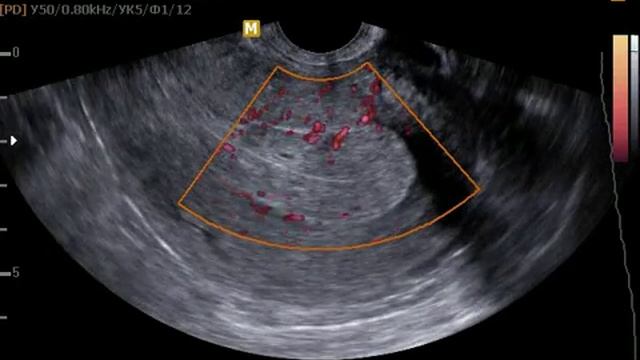

Эхогенность понижена матки

Эхогенность понижена матки 117 фото